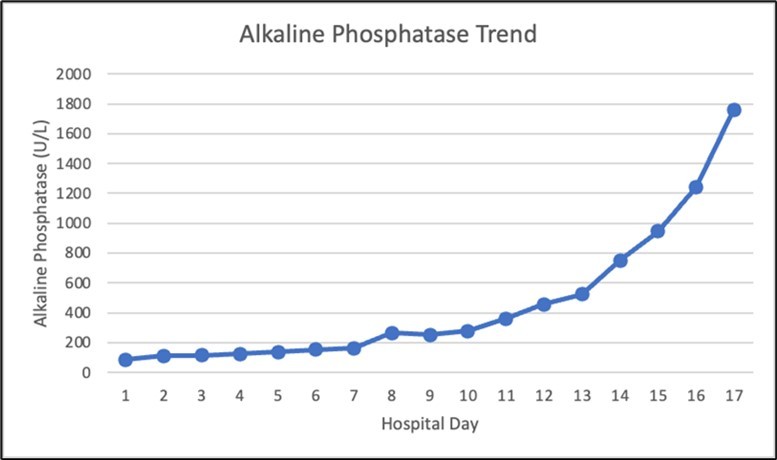

Figure 1.Alkaline phosphatase trend during the hospital course

A proton pump inhibitor infusion was started, and urgent upper endoscopy showed a 4 cm non-obstructing, deeply cratered duodenal ulcer with a large clot and diffuse oozing (Image 1). Hemostasis was achieved with the use of mineral powder that provides physical compression and promotes clotting. The lesion was not amenable to other forms of treatment given its size. She was subsequently extubated and transferred to the medical floor, where she had recurrence of melena. The patient’s melanotic stools self-resolved, but a continuously increasing alkaline phosphatase was noted, which prompted further workup (Figure 1).